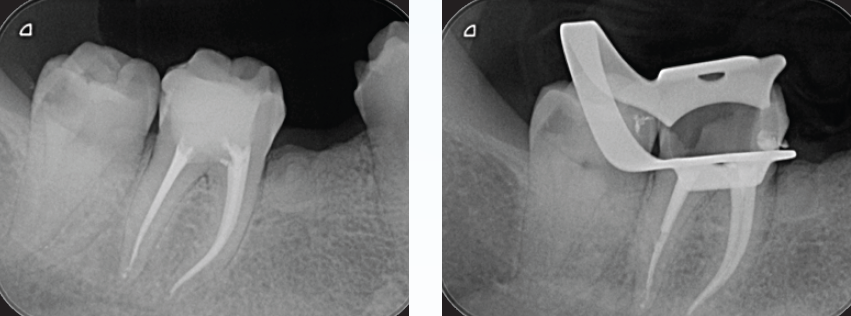

右下6番カリエスが進行し、遠心根根尖部周囲に透過像を認める(図9)。歯髄生活反応(―)

解剖学的形態は複雑な形態で湾曲度も強い。根管口付近の規制を除去してグライドパスを行い、根尖部に適度の抵抗形態を与えるためテーパー形成をニッケルチタンファイルを用いて根管拡大・形成を行った。MTAシーラーを併用しガッタパーチャを用いて根管充填を行った(図10)。

(図9)右下6番はカリエスが進行し、歯髄壊疽から遠心根根尖部に透過像を認める

歯髄腔は狭窄し近心根は複雑な湾曲を呈する

(図10)根管口付近の歯質を処理し、器具が歯軸に対して出来るだけ平行に挿入できるように

修正形成し根管処置を完了した

湾曲根管においてもトランスポーテーションすることなく、

本来の根管の形態を極力維持することができた